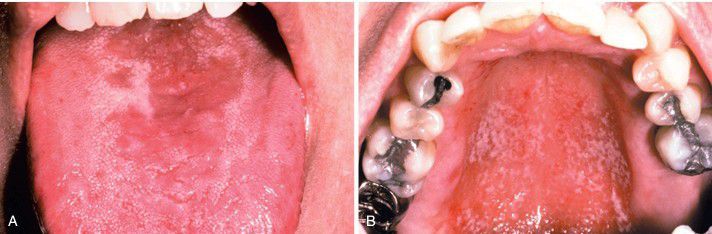

A, Multifocal oral candidiasis characterized by central papillary atrophy of the tongue and other areas of involvement. B, Same patient showing a “kissing” lesion of oral candidiasis on the hard palate.